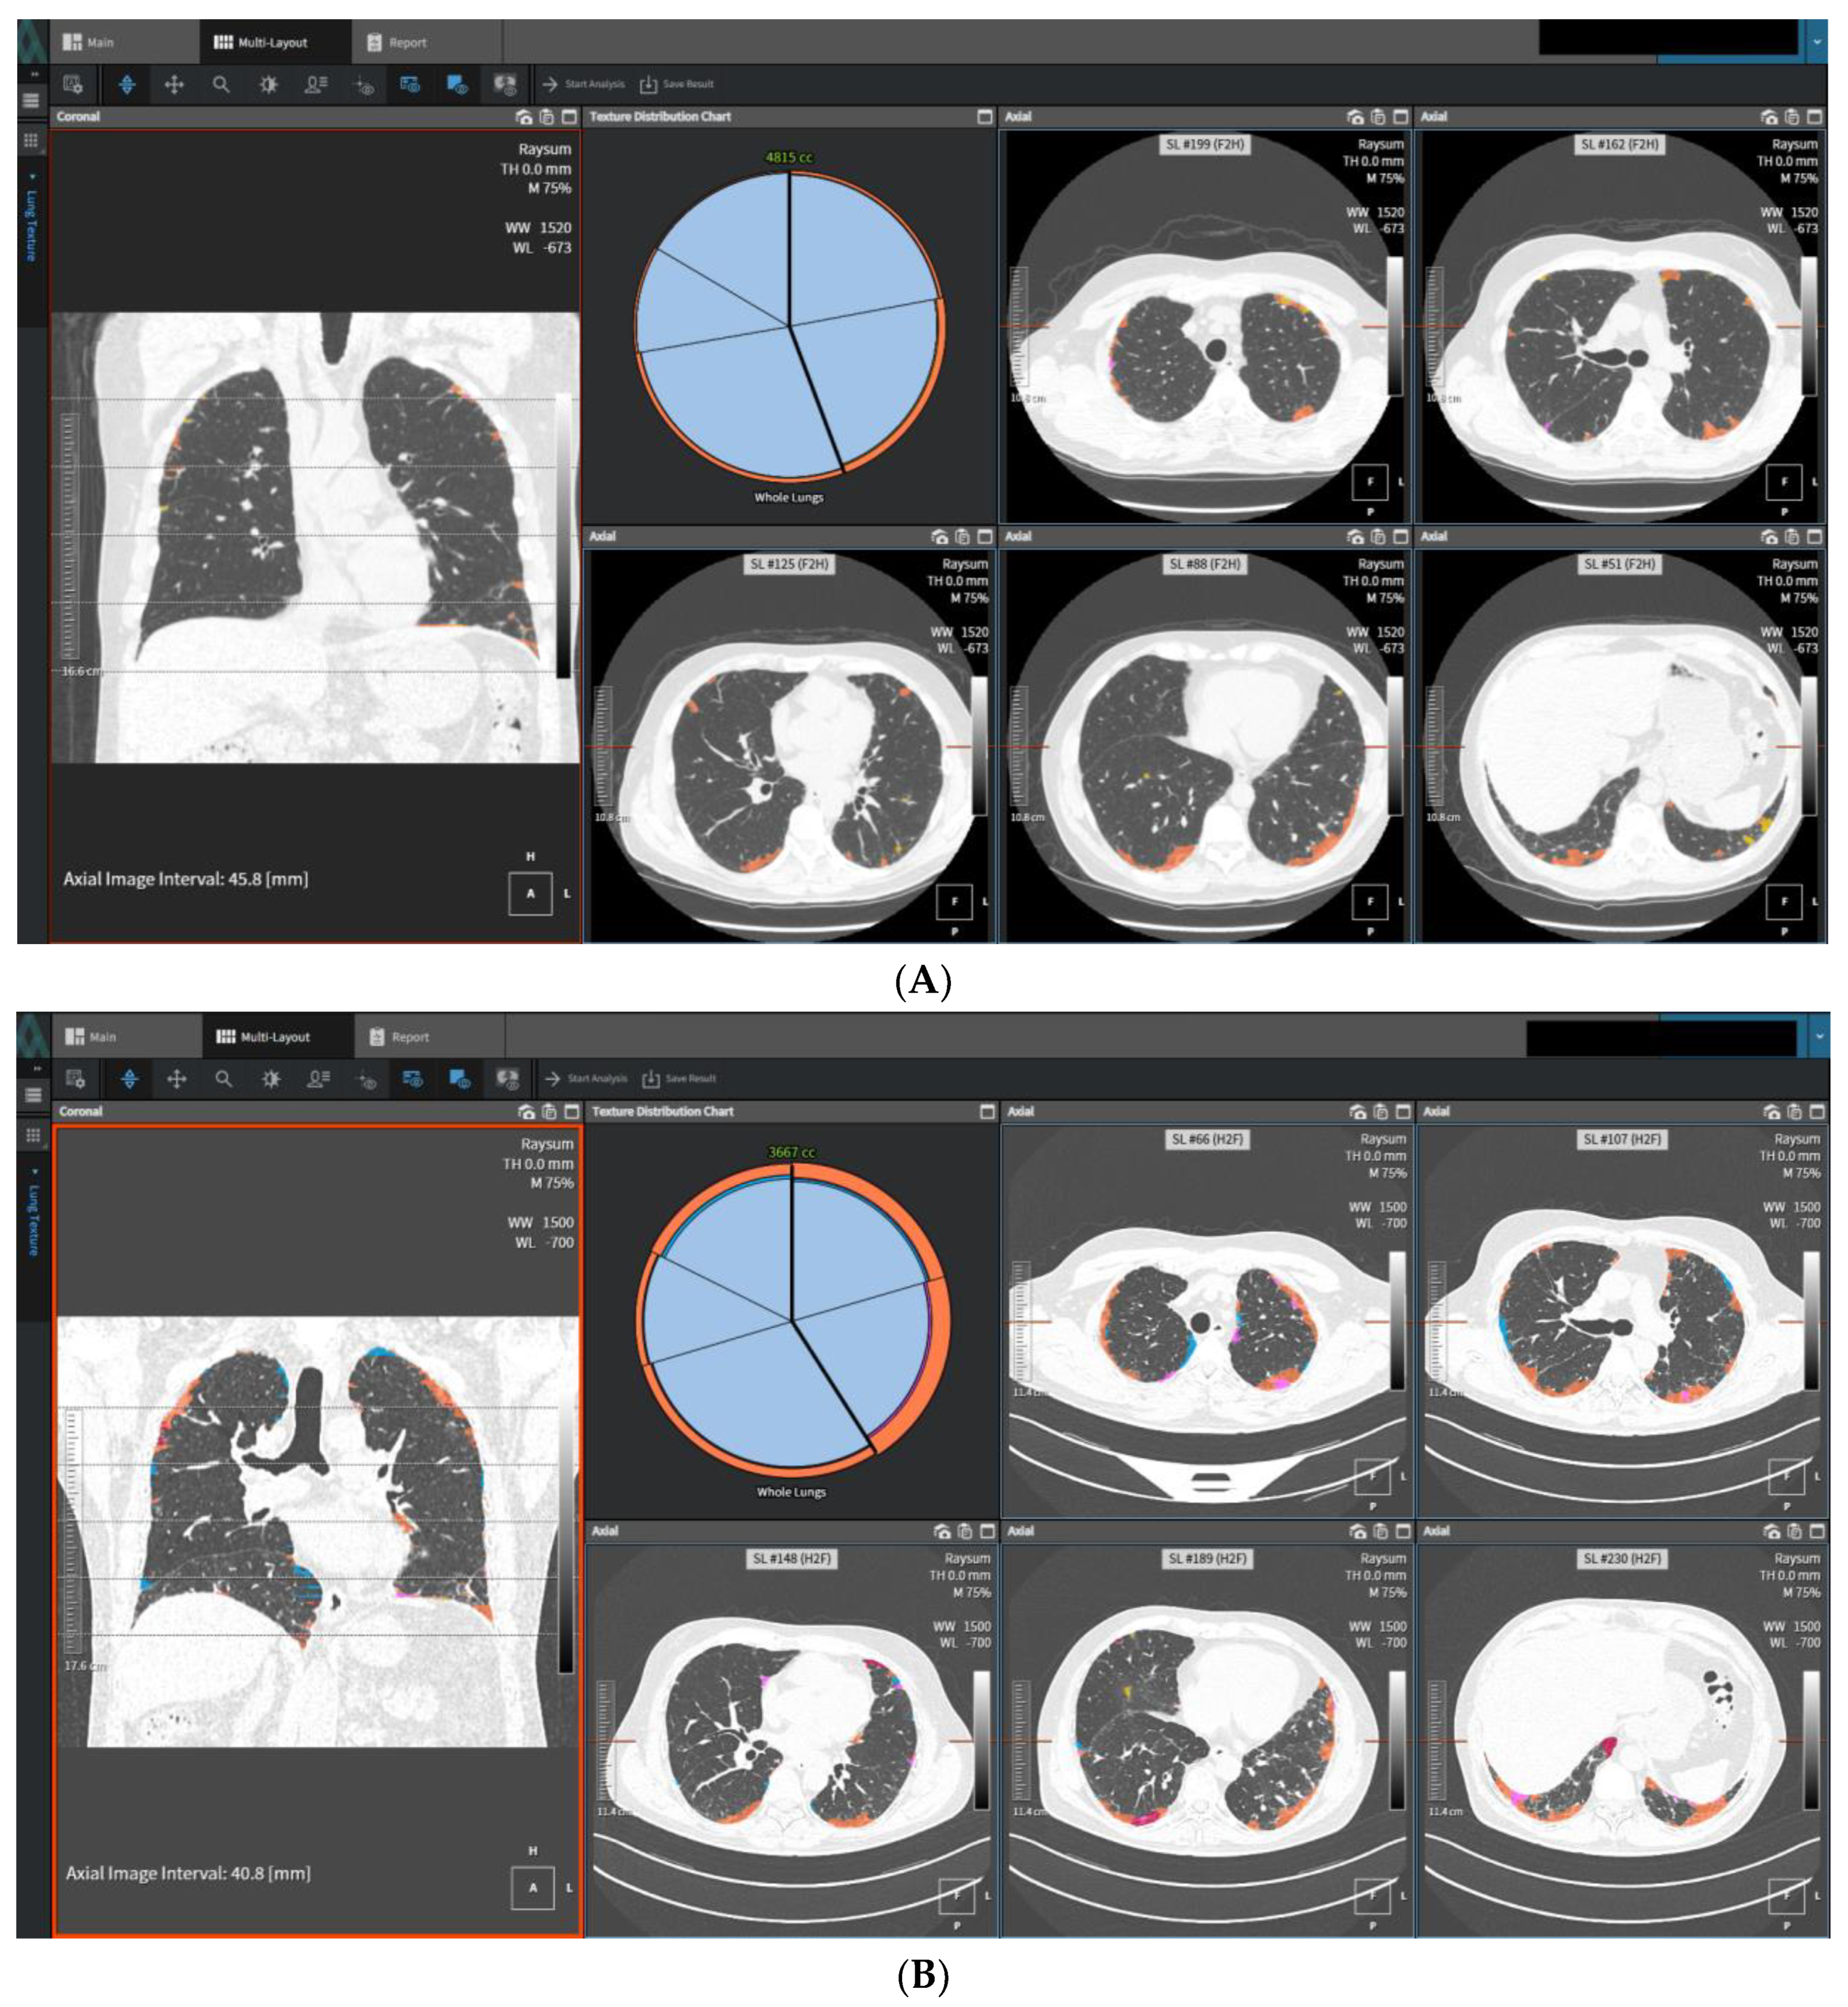

- Romei, C.; Falaschi, Z.; Danna, P.S.C.; Airoldi, C.; Tonerini, M.; Rocchi, E.; Fanni, S.C.; D′Amelio, C.; Barbieri, G.; Tiseo, G.; et al. Lung vessel volume evaluated with CALIPER software is an independent predictor of mortality in COVID-19 patients: A multicentric retrospective analysis. Eur. Radiol. 2022, 32, 4314–4323. [Google Scholar] [CrossRef]

- Silva, M.; Milanese, G.; Ledda, R.E.; Maddalo, M.; Sverzellati, N. Artificial Intelligence-Based Evaluation of Patients with Interstitial Lung Disease. In Artificial Intelligence in Cardiothoracic Imaging. Contemporary Medical Imaging; De Cecco, C.N., van Assen, M., Leiner, T., Eds.; Humana: Cham, Switzerland, 2022. [Google Scholar] [CrossRef]

- Suman, G.; Koo, C.W. Recent Advancements in Computed Tomography Assessment of Fibrotic Interstitial Lung Diseases. J. Thorac. Imaging, 2023; ahead of print. [Google Scholar] [CrossRef]